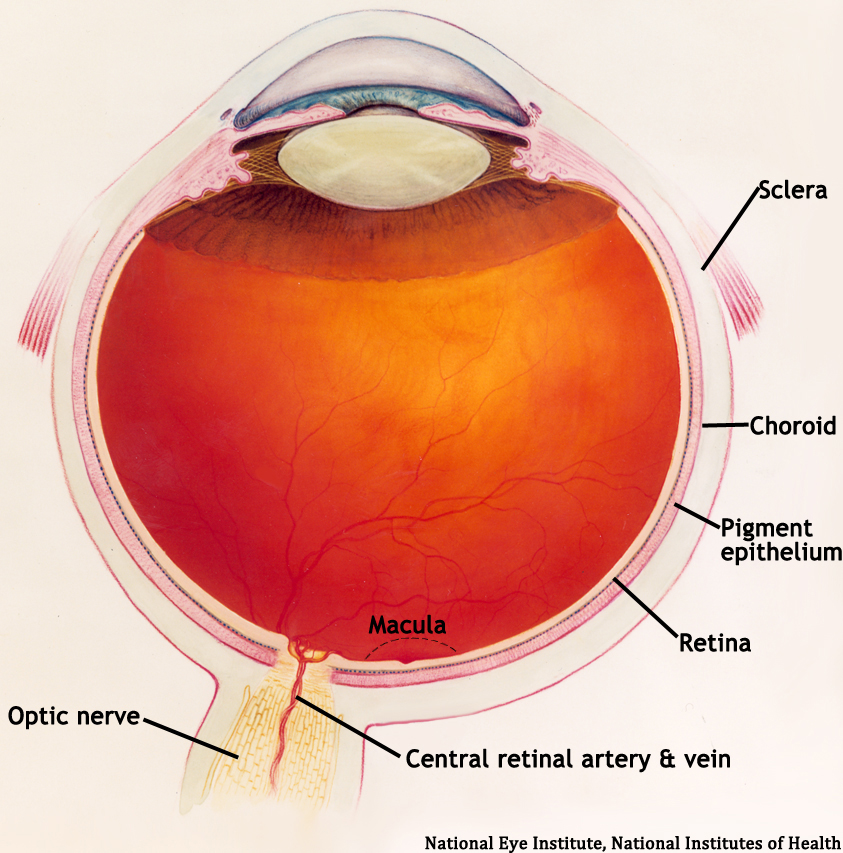

1 Anatomy of the Vitreous, Retina, and Choroid | Ento Key